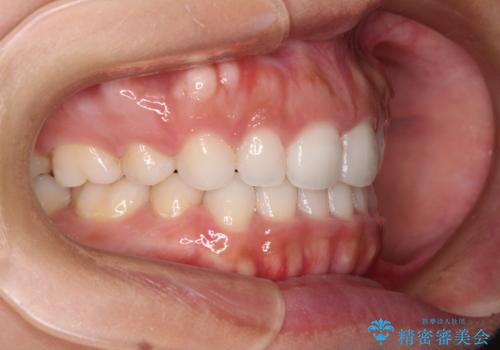

- 治療期間

- 2年9ヶ月

表側のワイヤー矯正に比べると治療期間は長く、費用も高額となりますが、どうしても目立たせたくないという方にはお勧めの抜歯矯正です。